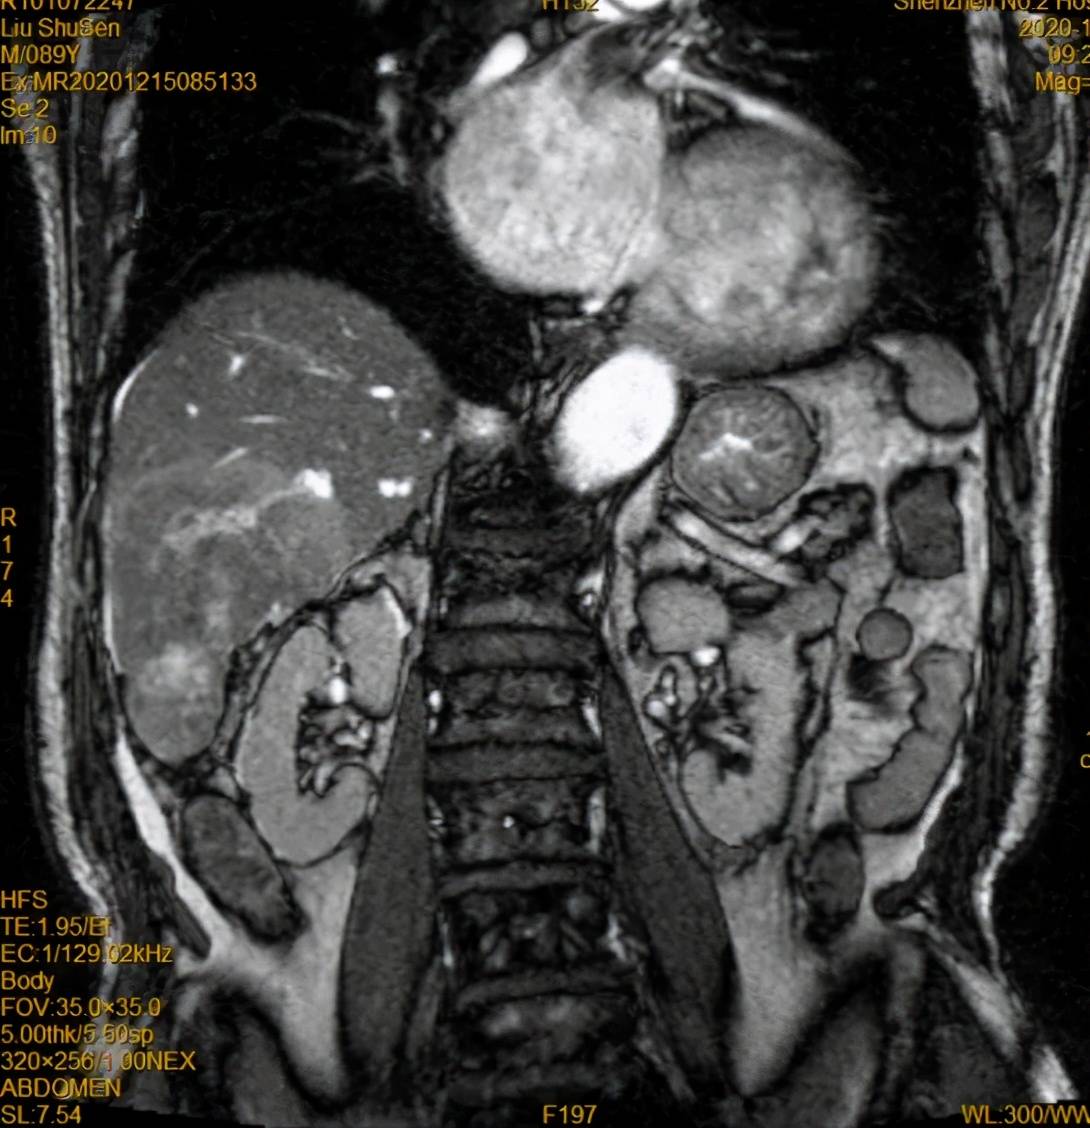

复查造影:原肿瘤染色不复显影

治疗后第2天 , 89岁的刘老伯就可以下床活动 。 术后3个月复查肿瘤标志物AFP明显下降 , 目前已正常 。 仅行介入治疗1次即达到CR(完全缓解 ) 。

经过详细检查 , 患者甲胎蛋白升高 , 腹部MR增强示肝脏肿物 , 铅球样大小 。 诊断为原发性肝癌(BCLC B期) , 伴肝硬化 。

2020-12-15 术前MR冠状位